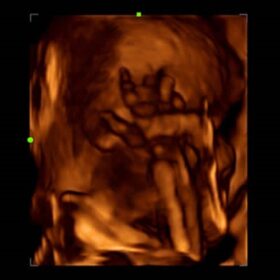

Ultrasound Mindray Z60 – Image Gallery

- 3D/4D imaging, Including 3D/4D Flip & Sync features providing fast and easy image volume view from any direction

- iLive, Integrating a ray-casting algorithm with a new virtual lighting modality, iLive generates an amazingly realistic view of the fetus with human skin-like images.

- Smart Face, The new Mindray Z60 provides a fast and intelligent optimization for fetal face with simply one-touch. It can immediately remove occlusions in the volume data, eliminate unwanted noise information, and generate an optimal view of the fetal face with minimal effort.